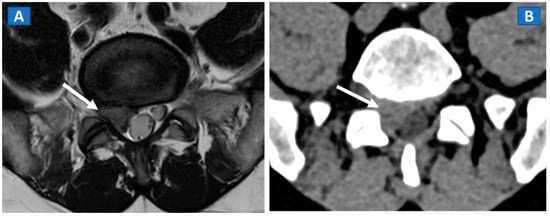

DECT can distinguish fresh from old vertebral compression fractures by demonstrating the presence of BME [11]. In a recent metanalysis evaluating 13 studies using MRI as reference for diagnosis, including 515 patients and 926 acute fractures, DECT overall sensitivity was 86.2% with a specificity of 91.2% and accuracy of 89.3% [18]. In addition, DECT can accurately determine the position of hardware inserted during spinal surgery, by reducing metallic artifacts. The high intrinsic contrast of DECT images also assists in determining a differential diagnosis, such as in cases of disc herniation (Figure 2).

Figure 2.

A 46-year-old male with non-traumatic, acute right sciatica pain. A large, right postero-lateral disk herniation (arrow) can be recognized at L5-S1 level both on the axial T2-weighted MR image (A) and on the corresponding axial 1 mm reconstructed CT image with a soft tissue window (B).